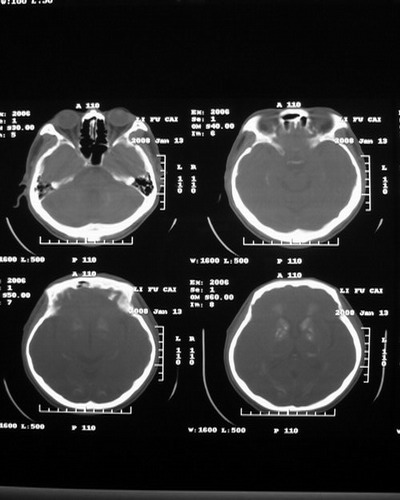

以下是引用随光逐影在2008-1-14 17:26:00的发言:[br]考虑为:甲状旁腺功能低下。需与fahr`s病相鉴别。建议:实验室检查。